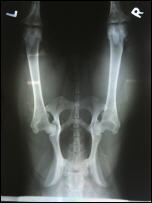

Allys Hüften

HD: A2/A2